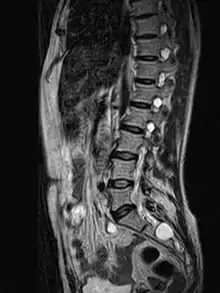

Tarlov cyst

Tarlov cysts, are type II innervated meningeal cysts, cerebrospinal-fluid-filled (CSF) sacs most frequently located in the spinal canal of the sacral region of the spinal cord (S1–S5) and much less often in the cervical, thoracic or lumbar spine. They can be distinguished from other meningeal cysts by their nerve-fiber-filled walls. Tarlov cysts are defined as cysts formed within the nerve-root sheath at the dorsal root ganglion.[2] The etiology of these cysts is not well understood; some current theories explaining this phenomenon have not yet been tested or challenged but include increased pressure in CSF, filling of congenital cysts with one-way valves, inflammation in response to trauma and disease. They are named for American neurosurgeon Isadore Tarlov, who described them in 1938.[3]

| MRI image showing a Tarlov cyst | |

Tarlov cysts are relatively uncommon when compared to other neurological cysts. Initially, Isadore Tarlov believed them to be asymptomatic, however as his research progressed, Tarlov found them to be symptomatic in a number of patients. These cysts are often detected incidentally during MRI or CT scans for other medical conditions. They are also observed using magnetic resonance neurography with communicating subarachnoid cysts of the spinal meninges. Cysts with diameters of 1 cm or larger are more likely to be symptomatic; although cysts of any size may be symptomatic dependent on location and etiology. Some 40% of patients with symptomatic Tarlov cysts can associate a history of trauma or childbirth.[4] Current treatment options include CSF aspiration, fibrin-glue therapy, laminectomy with wrapping of the cyst, among other surgical treatment approaches. Interventional treatment of Tarlov cysts is the only means by which symptoms might permanently be resolved due to the fact that the cysts often refill after aspiration. Tarlov cysts often enlarge over time, especially if the sac has a check valve type opening. They are differentiated from other meningeal and arachnoid cysts because they are innervated and diagnosis can in cases be demonstrated with subarachnoid communication.

MRI

MRI, or Magnetic Resonance Imaging, is considered the imaging study of choice in identifying Tarlov cysts. MRI provides better resolution of tissue density, absence of bone interference, multiplanar capabilities, and is noninvasive. Plain films may show bony erosion of the spinal canal or of the sacral foramina. On MRI pictures, the signal is the same as the CSF one.